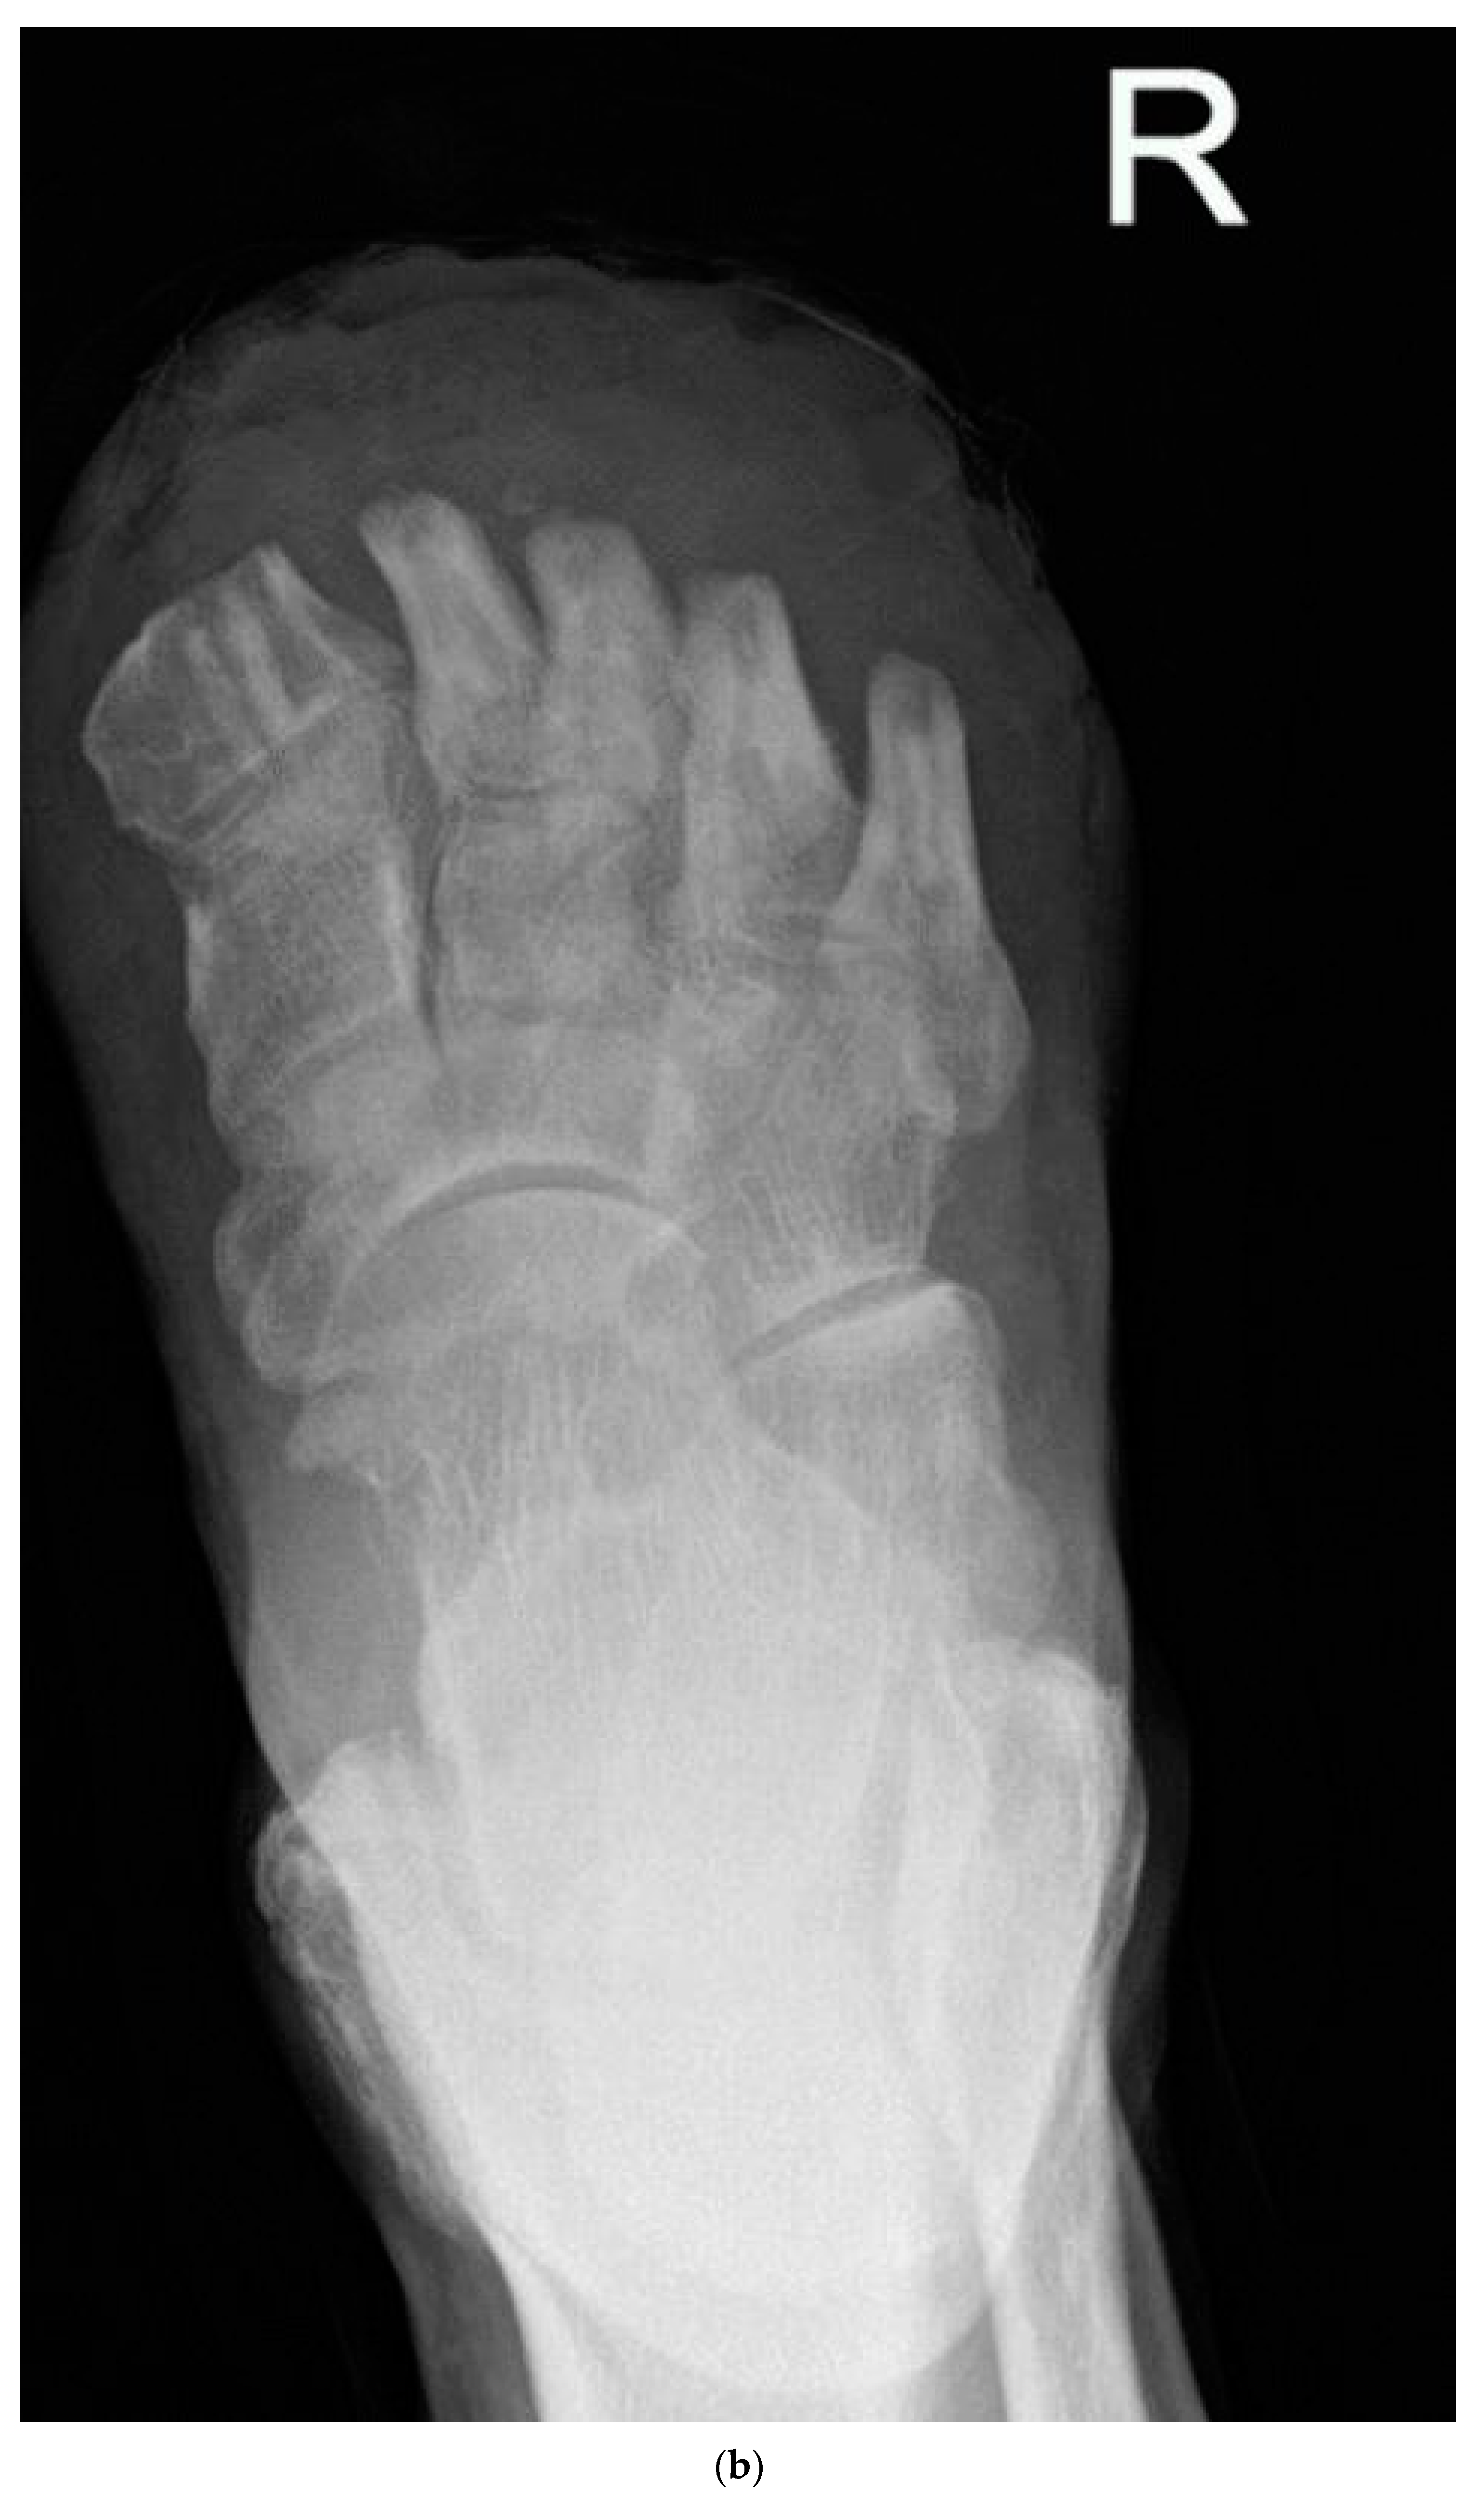

2.4. Surgical Management

- Kavarthapu, V.; Vris, A. Charcot midfoot reconstruction-surgical technique based on deformity patterns. Ann. Jt. 2020, 5, 28. [Google Scholar] [CrossRef]

- Kavarthapu, V.; Budair, B. Two-stage reconstruction of infected Charcot foot using internal fixation: A promising functional limb salvage technique. Bone Jt. J. 2021, 103, 1611–1618. [Google Scholar] [CrossRef]